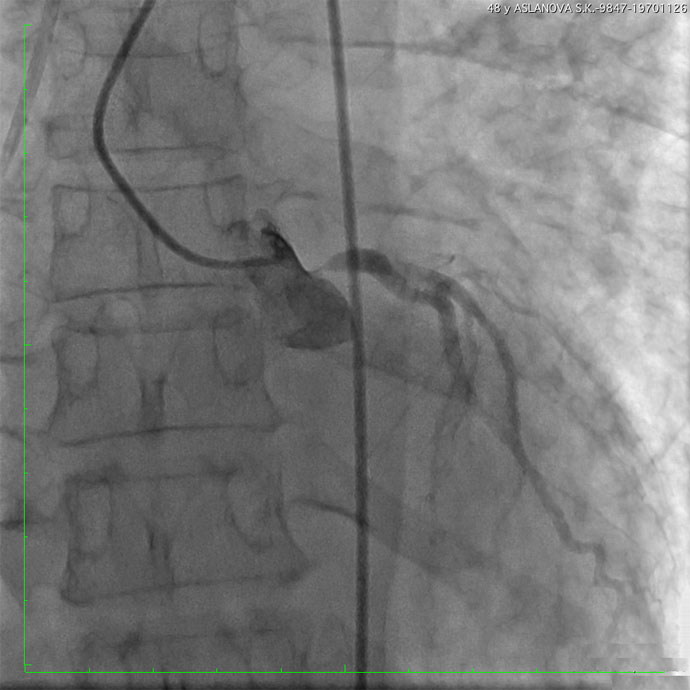

Обращали на себя внимание прогрессирующее снижение толерантности к физическим нагрузкам и эпизодические давящие, жгучие боли за грудиной. В результате проведенного обследования по данным ЭКГ выявлены ишемические изменения миокарда, по результатам КТ — признаки отека легких. Диагноз пневмонии не подтвердился. Проведена диагностика на предмет острой коронарной патологии: по результатам Эхо-КГ выявлено снижение общей систолической функции миокарда левого желудочка с нарушением его локальной сократимости. По лабораторным данным выявлено повышение уровня кардиоспецифических ферментов, указывающих на повреждение миокарда. После дообследования было принято решение о проведении экстренной коронароангиографии (КАГ).

В рентгеноперационной по результатам КАГ выявлен критический стеноз (сужение) ствола левой коронарной артерии и устья правой коронарной артерии — иными словами, практически отсутствовало кровоснабжение большого объема сердечной мышцы. Во время попытки реваскуляризации (восстановления кровотока) правой коронарной артерии у больной произошла остановка сердечной деятельности. Несмотря на проведение расширенного комплекса реанимационных мероприятий, сердечная деятельность не восстановилась, в связи с чем по жизненным показаниям для экстракорпорального поддержания жизни принято решение о применении механической поддержки кровообращения методом экстракорпоральной мембранной оксигенации (ЭКМО). Была проведена имплантация системы бивентрикулярного обхода желудочков сердца (Cardiohelp)) для протезирования сердечной функции. Аппарат ЭКМО выполнял функцию искусственного сердца и позволил прекратить непрямой массаж, несмотря на отсутствие сокращений миокарда. На фоне процедуры вено-артериальной ЭКМО выполнена баллонная ангиопластика со стентированием коронарных артерий.

— У больной выявлено сочетание поражение двух основных артерий сердца. Реваскуляризация миокарда у таких пациентов сопряжена с высоким риском развития фатальных осложнений. У нашей пациентки произошла рефрактерная (устойчивая к терапии) остановка кровообращения. Реанимационные мероприятия продолжались больше 20 минут, пока специалисты центра ЭКМО устанавливали систему экстракорпорального поддержания жизни. Система ЭКМО обеспечивала ток крови, минуя сердце, и насыщение ее кислородом, на этом фоне было выполнено стентирование устья правой коронарной артерии — установлено 2 стента, и ствола левой коронарной артерии — 1 стент, в результате кровоток по обеим артериям был восстановлен.